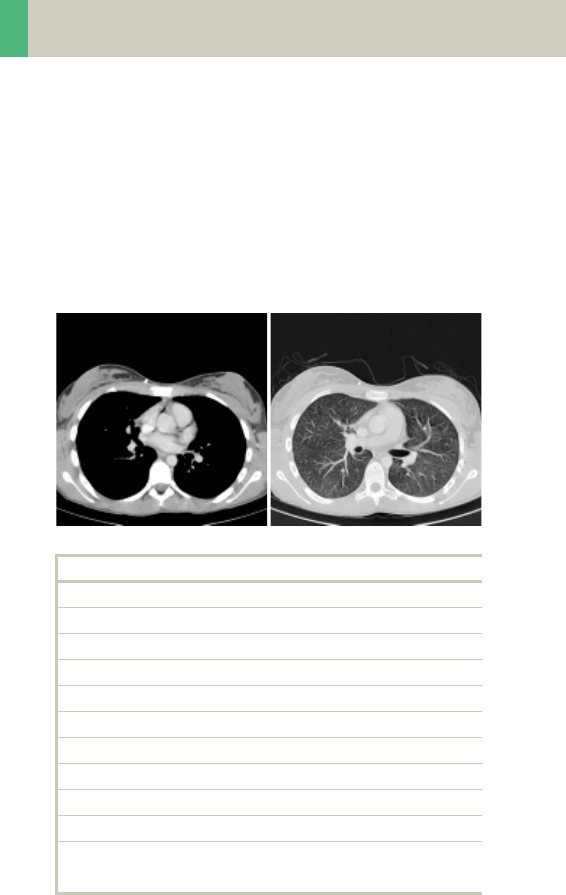

ThorAngio/ThorAngio08s

Indications:

Spiral study for location and extent of aneurysms, dis-

section, and ruptures of the thoriac aorta.

A range of 20 cm will be covered in 24/19 sec.